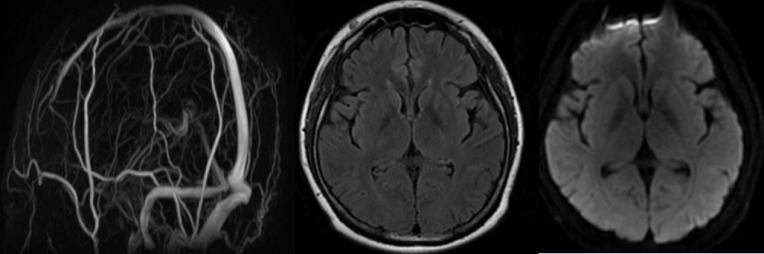

• 头颅CT:双侧枕叶低密度水肿灶(图1)。

image.png

1 头颅CT(2025年6月22日